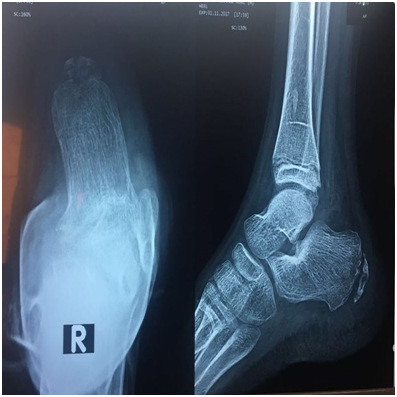

The ultrasonography demonstrated fragmentation of the apophysis of the calcaneus and an avulsed bone fragment at the insertion of the Achilles tendon (Figure 3) together a well-defined echogenic fluid collection with high Doppler signals on both sides of tendo-achilles (Figure 4). Ultrasonographic guided needle aspiration of the fluid collection was performed, the Culture of the aspirated fluid revealed Staphylococcus aureus. The X-ray showed Fragmentation of calcaneal apophysis & few osteolytic lesions (Figure 5). Echocardiography was normal. Further evacuation was done surgically and antibiotic was started with marked improvement of the patient condition.

Figure 5 legend   x-ray of Rt heel show evidence of osteomyelitis.